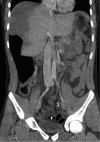

Paintball is a popular recreational sport played at both amateur and professional level. Ocular injuries are well recognised, although there is a growing body of literature documenting superficial vascular as well as deep solid organ injuries. An 18-year-old man presented with signs and symptoms consistent with acute appendicitis. Intraoperatively, a grade III liver injury was identified and packed before a relook at 48 h. No further active bleeding was identified; however, follow-up ultrasound at 3 weeks demonstrated non-resolution of a large subcapsular haematoma. The patient was readmitted for a short period of observation and discharged with repeat ultrasound scheduled for 3 months. This represents the first report of paintball-related blunt traumatic injury to the liver. Solid organ injuries of this nature have only been reported three times previously-all in the urological setting. This case also highlights issues surrounding the use of routine follow-up imaging in blunt liver trauma and provides a concise discussion of the relevant literature.